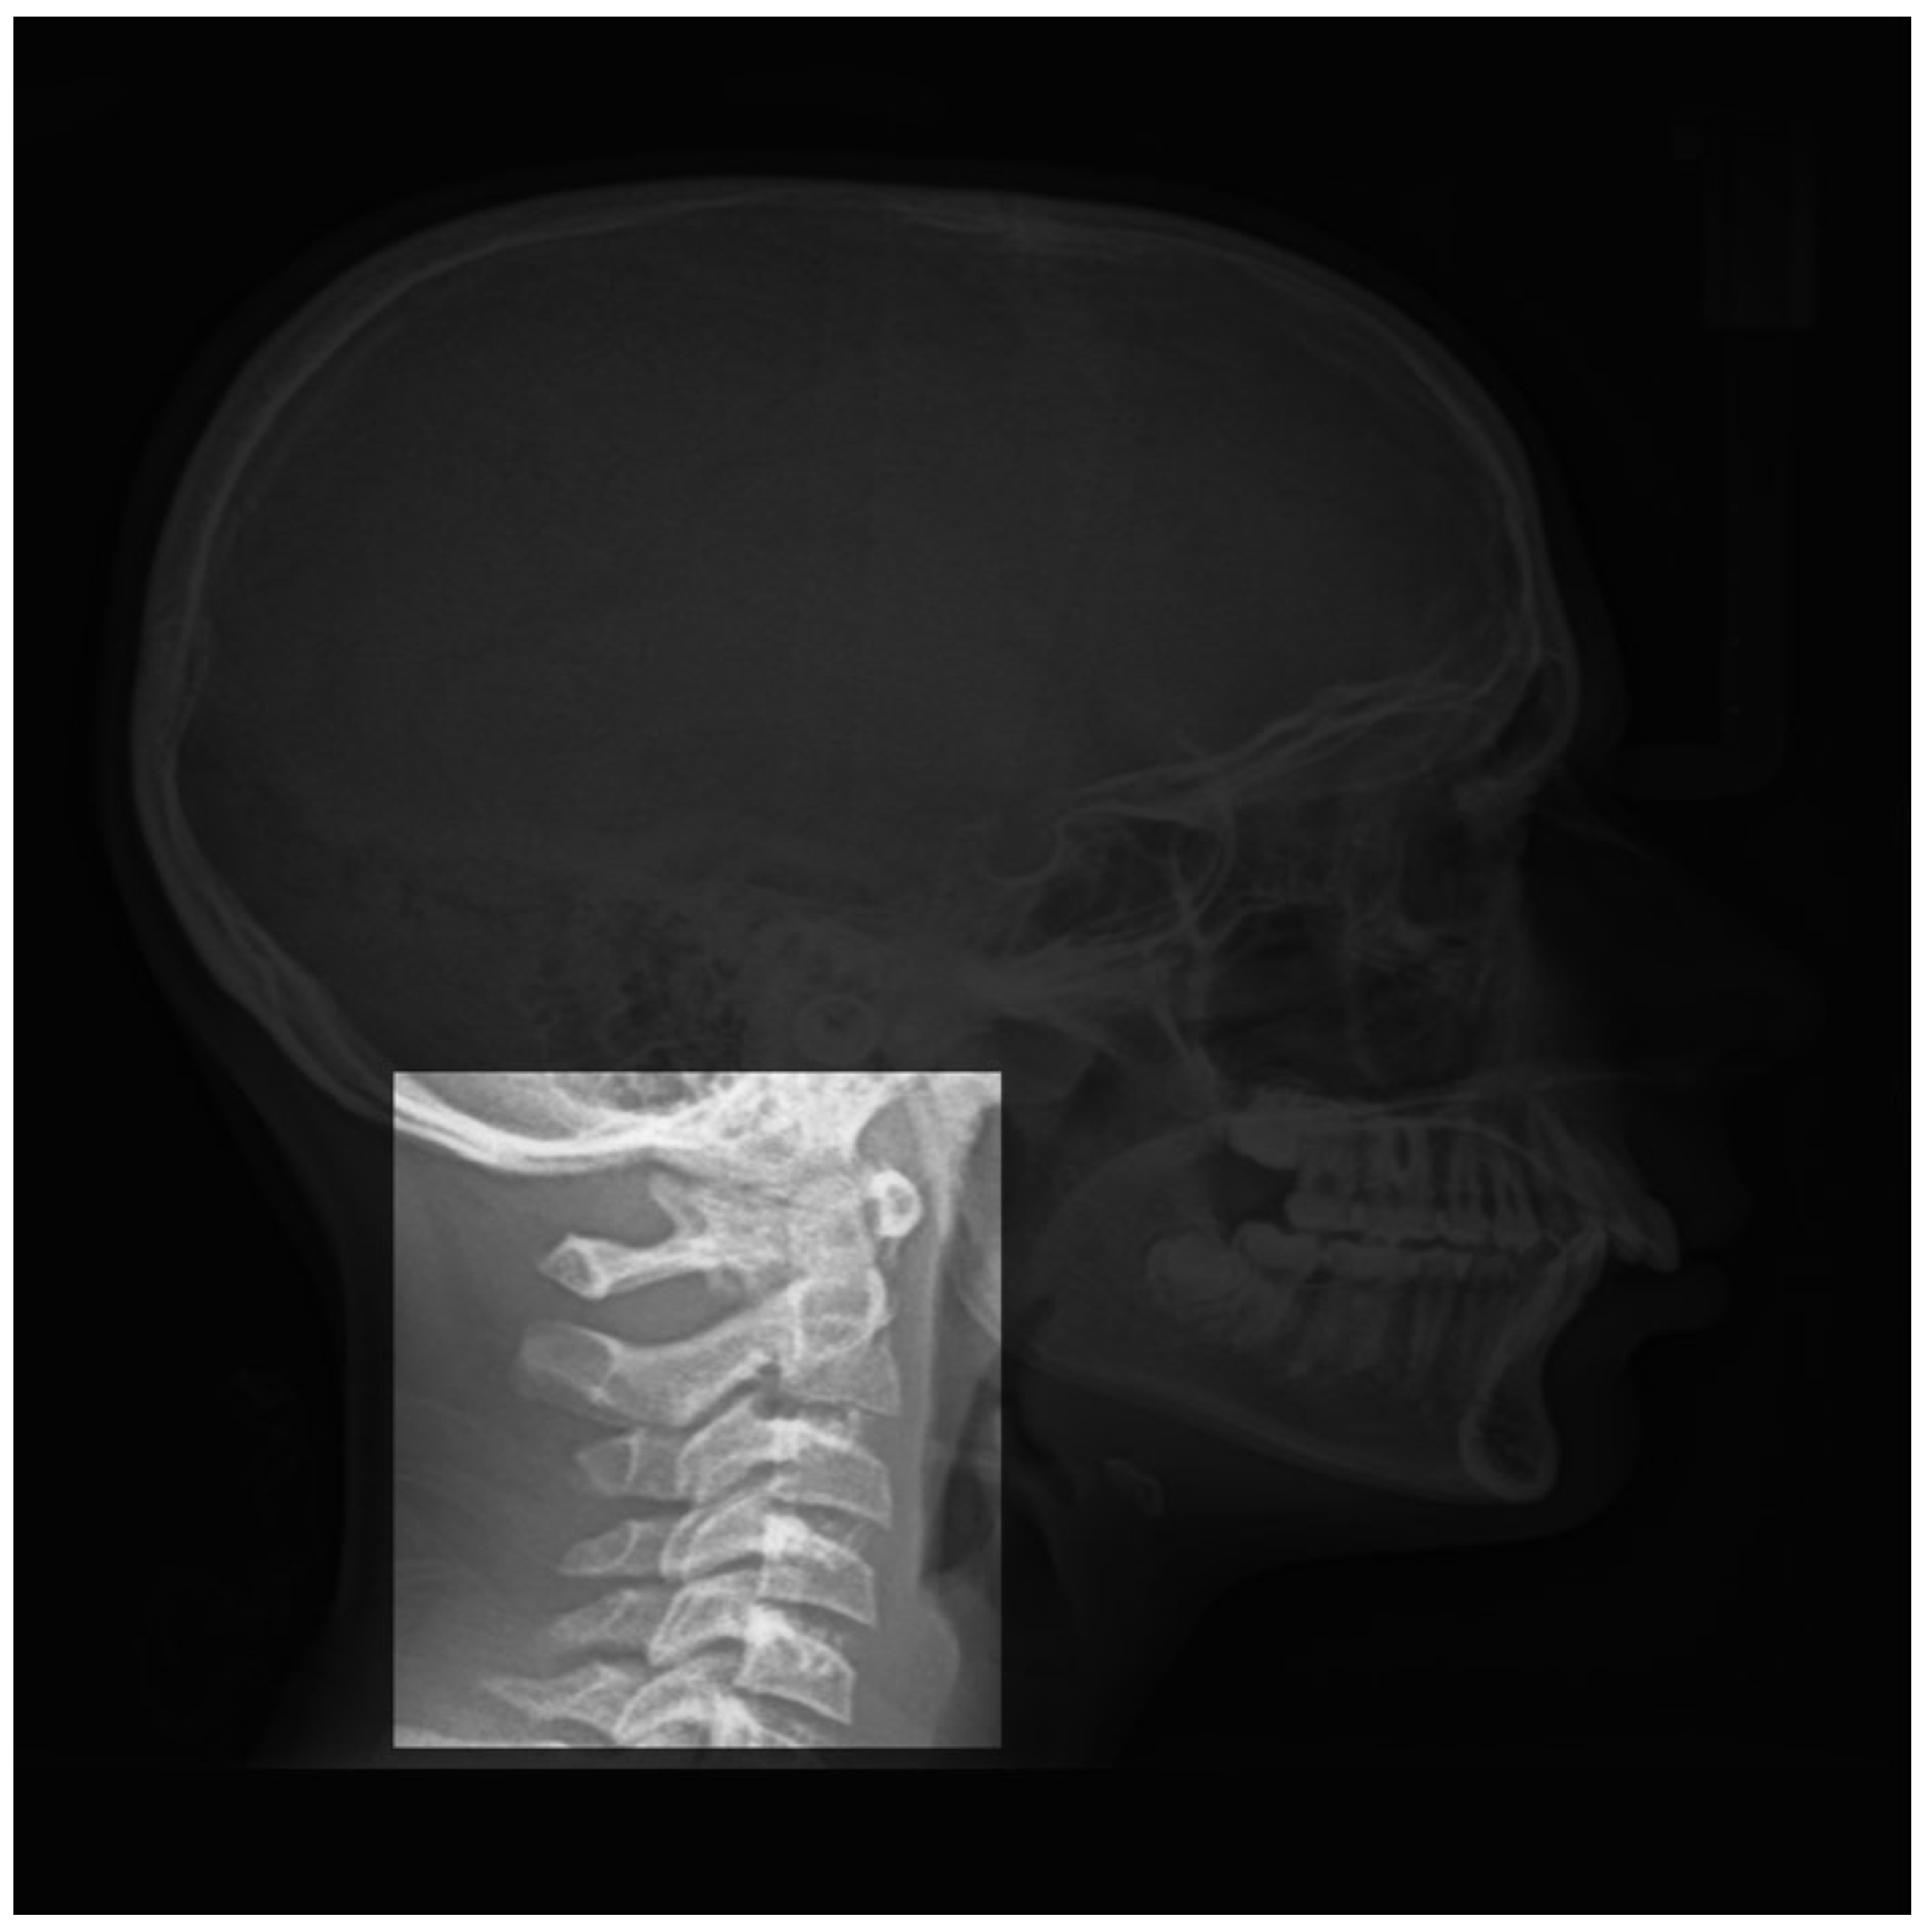

3.2. Vertebrae Maturation CVM:

- Cervical stage 1 (CS1) = 2 years before mandibular growth peak:Lower borders of C2 to C4 vertebrae are flat. C3 and C4 superior borders are tapered from posterior to anterior.

- Cervical stage 2 (CS2) = 1 year before mandibular growth peak:Lower border of C2 presents a concavity. Bodies of C3 and C4 are the same.

- Cervical stage 3 (CS3) = during the year of the mandibular growth peak:Lower borders of C2 and C3 present concavities. Vertebrae are growing so C3 and C4 may be either trapezoid or rectangular shape, as superior borders are less and less tapered.

- Cervical stage 4 (CS4) = 1 or 2 years after mandibular growth peak:Lower borders of C2, C3 and C4 present concavities. Both C3 and C4 bodies are rectangular with horizontal superior borders longer than higher.

- Cervical stage 5 (CS5) = 1 year after the end of mandibular growth peak:Still concavities of lower borders of C2, C3 and C4. At least one of C3 or C4 bodies are squared and spaces between bodies are reduced.

- Cervical stage 6 (CS6) = 2 years after the end of mandibular growth peak:The concavities of lower borders of C2 to C4 have deepened. C3 and C4 bodies are both square or rectangular vertical in shape (bodies higher than wide)